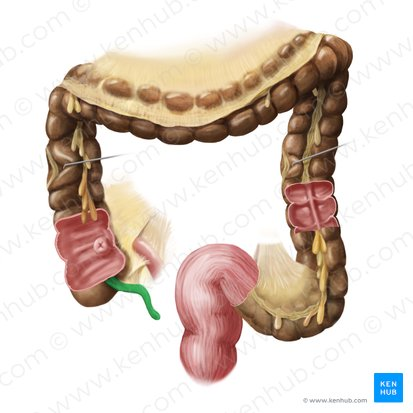

Mesocolon

A fold of peritoneum that attaches the colon to the posterior abdominal wall.

Right Colonic Flexure (Hepatic Flexure)

The bend in the large intestine where the ascending colon becomes the transverse colon, located on the right side of the abdomen.

Ascending Colon

The part of the large intestine that travels upward from the cecum along the right side of the abdomen.

Ileocecal Valve

A sphincter muscle situated at the junction of the ileum and the cecum, which controls the flow of chyme from the small intestine into the large intestine and prevents backflow.

Cecum

A pouch-like structure connected to the junction of the small and large intestines.

Appendix

A small, finger-like pouch attached to the cecum.

Ileum

The final and longest section of the small intestine, which absorbs vitamin B12, bile salts, and any remaining nutrients.

Jejunum

The middle section of the small intestine, where most of the digestion and absorption of carbohydrates, lipids, and proteins occurs.

Transverse Colon

The part of the large intestine that travels across the abdomen from right to left.

Left Colonic Flexure

The bend in the large intestine where the transverse colon becomes the descending colon, located on the left side of the abdomen.

Taenia Coli

Three longitudinal bands of smooth muscle on the outer surface of the large intestine that create haustra.

Descending Colon

The part of the large intestine that travels downward along the left side of the abdomen.

Haustrum

A pouch-like sacculation in the wall of the large intestine, formed by the contraction of the taenia coli.

Internal Anal Sphincter

A thickened ring of smooth muscle that surrounds the anal canal. It is under involuntary control, meaning you don't consciously control its contraction or relaxation. It is normally contracted to maintain fecal continence.

Rectum

The final section of the large intestine, terminating at the anal canal. Its primary function is to store feces before they are eliminated from the body.

External Anal Sphincter

A ring of skeletal muscle that surrounds the anal canal, superficial to the internal anal sphincter. It is under voluntary control, meaning you can consciously choose to contract or relax it to control the passage of feces. This allows for the postponement of defecation.

Anus

The opening at the end of the digestive tract through which feces are eliminated from the body. It is surrounded by the internal and external anal sphincters, which regulate the passage of waste.